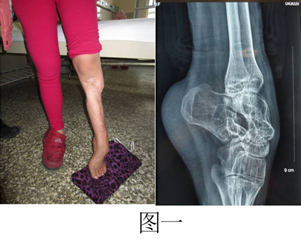

病例一:患者女,13岁,因“左足外伤术后内翻畸形伴下肢短缩五年”入院。检查患者左小腿瘢痕挛缩,左踝关节僵硬,左足下垂内翻畸形,下肢短缩5cm(图一)。应用Ilizarov技术在胫骨截骨的基础上缓慢牵伸延长骨段,恢复肢体正常的长度,同时矫正足下垂(图二),是一期手术解决了两个不同的问题,节省病人的花费,取得满意的效果。患者拆除环形外固定架后肢体恢复长度和矫正马蹄足的体表情况(图三)。